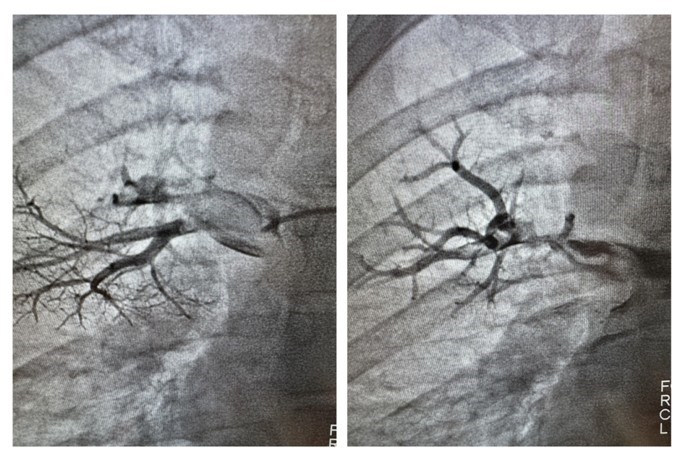

Применяемая в 20-й больнице методика позволяет врачам через один прокол проникнуть в венозную сеть, откуда через сердце добраться до легочной артерии и ее ветви. Тромб разрушается на фрагменты. Это позволяет быстрее его растворить и избежать тяжелых осложнений за счет сокращения времени и снижения количества препарата. Врач наблюдает за процессом с помощью ангиографа. Для этого пациенту в кровь вводят контрастное вещество.

«Такая операция длится от получаса до двух часов, зависит от сложности доступа к тромбу, количества изгибов сосудистого русла, по которым нужно пройти, объема действий, которые нужно выполнить врачу-оператору. Есть тромбы очень податливые, которые буквально разрушаются на глазах. Есть такие, с которыми приходится изрядно повозиться. Как только удается разрушить тромб, в область тромбоза или непосредственно в тромбомассы вводится тромболитик, который завершает процесс» рассказали в минздраве.